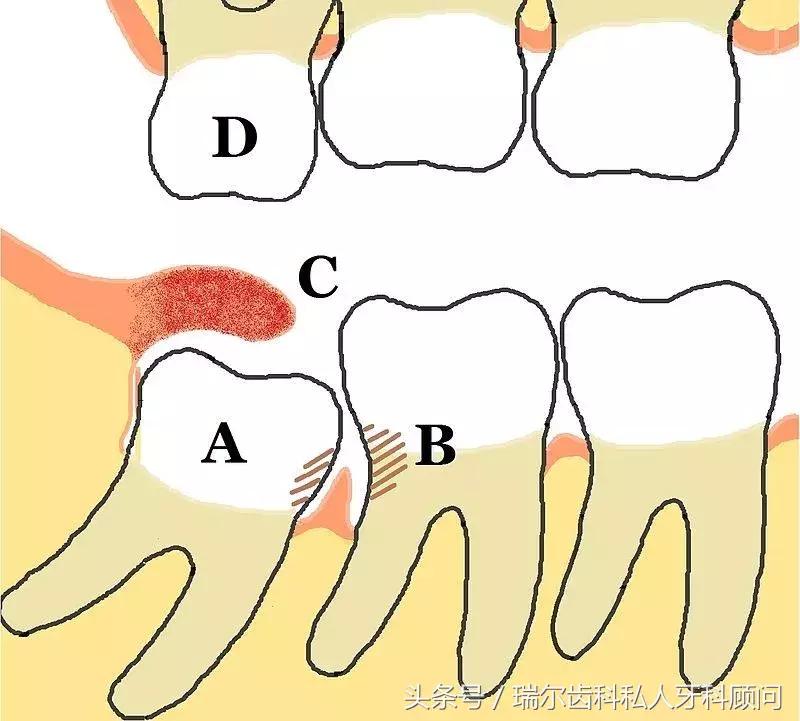

智齿会毁了你的第二磨牙。那些靠着第二磨牙(与智齿相邻的牙齿)牙根生长的智齿,会在萌出时产生作用于第二磨牙牙根表面的破骨细胞,使牙根逐渐吸收,破坏牙神经,引起疼痛,甚至脱落。此外,智齿阻生或错位,会导致与第二磨牙形成卫生死角,不易清洁,久而久之引发第二磨牙龋齿。

智齿冠周炎反复发作。当智齿萌出受阻,牙龈组织在智齿周围形成牙龈袋(下图红肿的位置),细菌在此繁殖生长,一旦出现创伤或免疫力受损,炎症便会找上门,牙龈肿胀疼痛;若不及时治疗,感染继续扩散,将会出现面部肿胀、发烧、张不开嘴等症状。

↑ 示意图